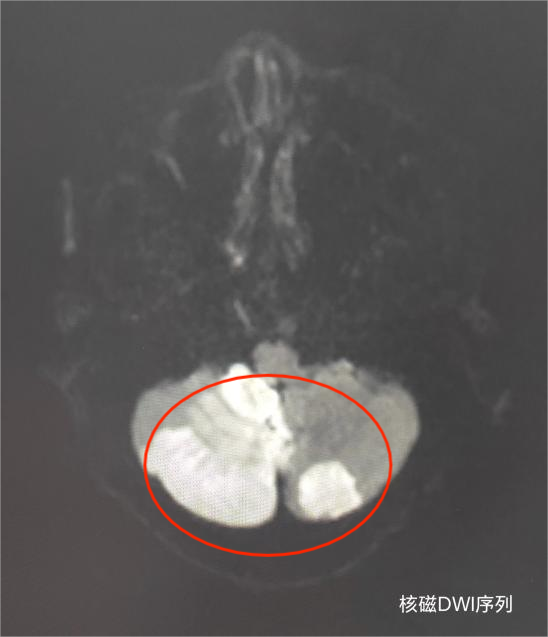

中风患者在我院影像科进行头颅核磁共振检查,发现小脑大面积急性脑梗死影像。